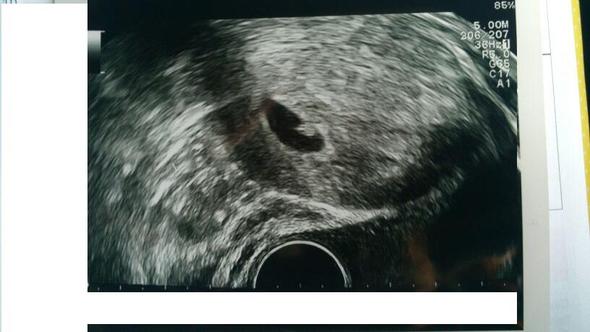

Eine Fruchthöhle mit einen Embryo oder einer Struktur, die zu der Fruchtanlage gehört (Dottersack) ist mit einem guten UltraschallGerät etwa ab der 5 bis 6 Schwangerschaftswoche möglich Vielleicht ist deine Schwangerschaft einfach noch nicht so weit fortgeschritten, wie du denkst.

Antwort Eine Schwangerschaft kann dann sicher nachgewiesen werden, wenn in der Gebärmutter eine Fruchthöhle mit einen Embryo oder einer Struktur, die zu der Fruchtanlage gehört (Dottersack), zu sehen ist Das ist mit guten UltraschallGeräten etwa ab der 5 bis 6 Schwangerschaftswoche möglich, also ab einer Woche nach Ausbleiben der Regel. Ein sicherer Nachweis der Schwangerschaft über Ultraschall ist aber erst ab der sechsten Schwangerschaftswoche möglich Trotzdem ist auch jetzt schon etwas im Ultraschall zu auszumachen Der Embryo sieht auf dem Bild wie ein Punkt aus, der etwa die Größe eines Stecknadelkopfs hat 6 Woche 4 Woche Zurück zur Übersicht Diese Artikel. Was bedeutet 6 SSW?.

6 woche schwanger ultraschall. Die meisten Frauen suchen etwa zwischen der 6 und 8 Schwangerschaftswoche (8 SSW) den Frauenarzt auf, um die Schwangerschaft bestätigen zu lassen Wenn Sie möchten, kann Ihr Partner zu dem Termin mitkommen. Sie ist in einer Woche von 6mm auf 11mm gewachsenLeider kann man aber keine "Babyumrisse" sehen Mein HCG Wert hat sich von 400 auf über 4000 erhöht, allerdings ist mein Progesteronwert gesunken Mein Arzt meint nun, dass ich vielleicht noch gar nicht in der 6 SSW bin, dass kann aber nicht sein, weil wir danach keinen Verkehr mehr hatten. Das allererste Zeichen einer intrauterinen Schwangerschaft, das wir im Ultraschall erkennen, ist die meist kreisrunde, echoarme Struktur, die im Ultraschalljargon „Fruchtsack“ genannt wird Der Fruchtsack entsteht zwar durch den Embryo, er ist genau genommen ein vom mütterlichen Endometrium gebildetes „Drumherum“, in dem sich die.

In der 6SSW ist eine rasante Entwicklung des Babys im Bauch der Mutter zu erkennen, die sich in zunehmenden Schwangerschaftssymptomen äußert Nachdem in der 5SSW das Herz zu schlagen begonnen hat, nimmt nun in der 6 SSW auch die Größe des Babys an Volumen zu, das Gehirn entwickelt sich weiter und die Gliedmaßen und Organe nehmen mehr Form an, was zum Teil auch im Ultraschall sichtbar wird. Bei jedem Wurf bringen Katzen zwischen 6 und 8 Kätzchen zur Welt Das ist ebenfalls von der Rasse und anderen Faktoren abhängig Während der Schwangerschaft nehmen Katzen zwischen 1 und 2 Kilo an Gewicht zu Nach ca 40 en kann per Ultraschall beim Tierarzt herausgefunden werden, wie viele Kätzchen es werden. Hallo, Habe letzte Woche Montag einen Schwangerschaftstest gemacht dieser war nur ganz leicht Positiv lautlachen Da ich mir nicht sicher war bin.